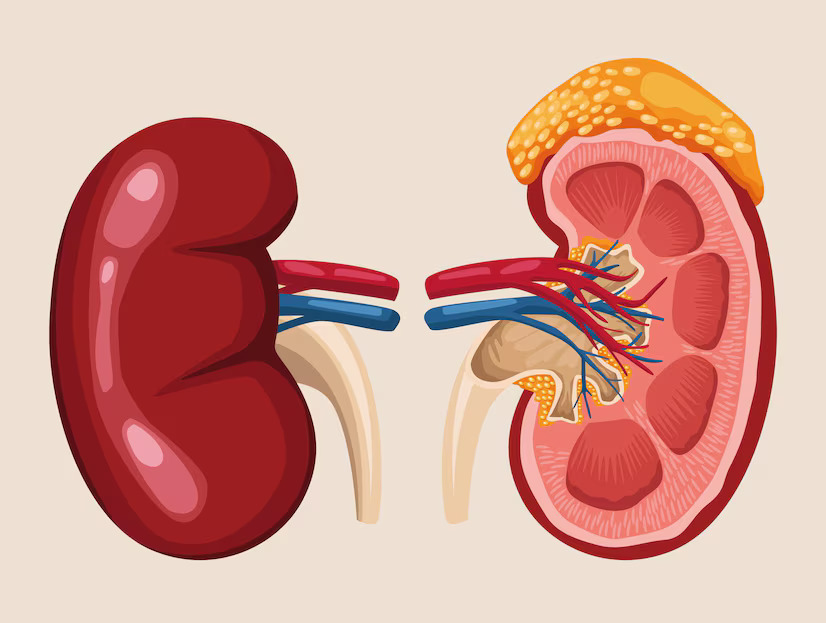

Congenital Kidney Disorders

Known as CAKUT (Congenital Anomalies of Kidney and Urinary Tract), these are structural defects present from birth. They range from a blockage in urine flow to babies born with a single kidney. Early surveillance ensures normal development.

Common Types

- Hydronephrosis (Swelling)

- PUV (Valve blockage)

- Polycystic Kidney Disease

- Single/Horseshoe Kidney